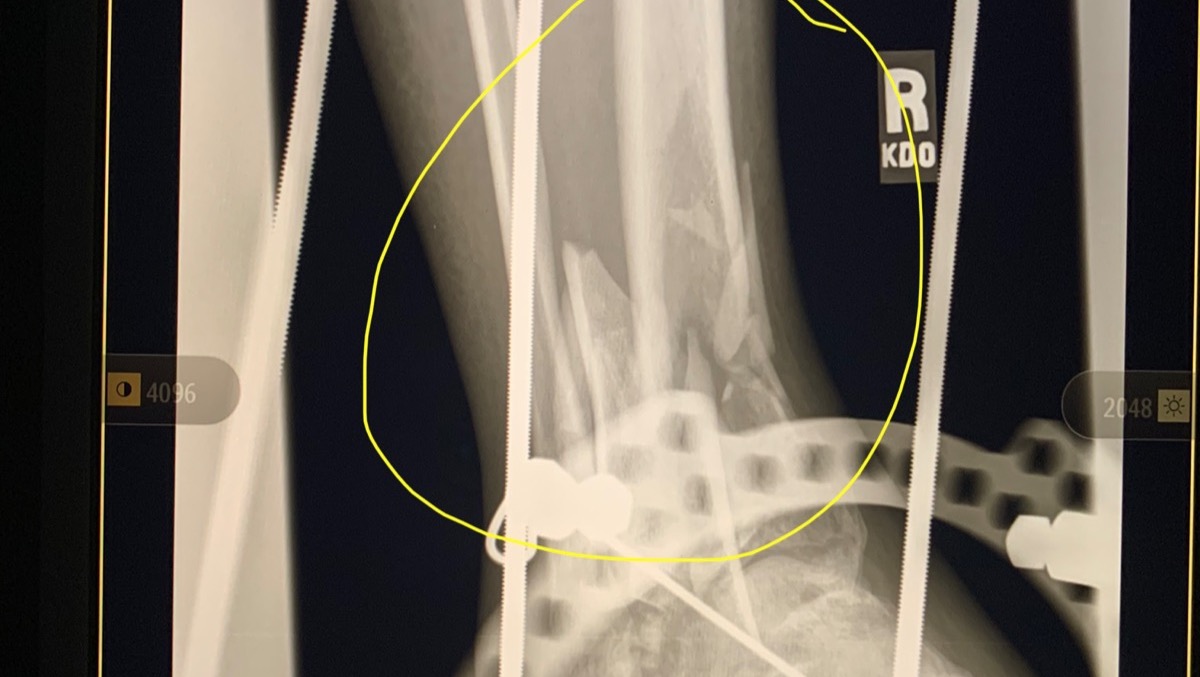

In 2007, I was in a near fatal accident and fell off of a 20 foot bridge. I was rushed to the hospital where they put me in a drug induced coma for two weeks. When I woke up I had an “external fixator” on my right leg and foot with rods and pins sticking out everywhere. My right tibia and fibula were broken and both feet were shattered. My left foot had a steel plate secured with seven screws. My right foot had an “Ex-fix” secured with rods and pins. My left wrist was shattered and required five pins to put back together. My back was broken as well and had to be fused together at L4-S1 with more rods and screws.

As you can see, I had a really bad day! I subsequently spent  three years in a wheelchair before my right leg and foot were strong enough for the fusion surgery that I had in January 2010. It was then a steel plate and ten screws were put in my right foot. So that gets me out of the wheelchair, but I had to learn how to walk again. That is, I had to learn coordination / balance skills all over again.